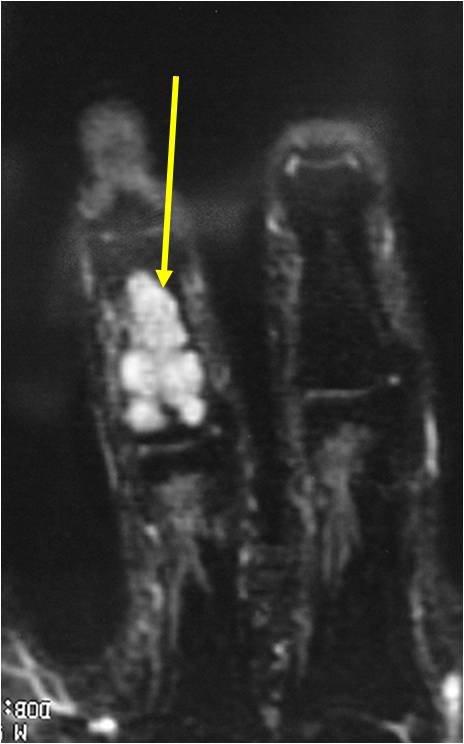

MRI:

- Lobulated margin (Lobular Growth Pattern)

- T2 Weighted Images: High Signal Intensity

- High water content shows as high signal on T2 weighted images

- Calcifications will be low signal

- Marked increased intensity long TR images

- There should never be any cortical destruction nor a soft tissue component. If this exists then the tumor must be a chondrosarcoma.

- Endosteal scalloping and cortical expansion is acceptable for phalangeal tumors. In most benign long bone cartilage tumors there is minimal endosteal scalloping but there should be no cortical expansion nor thickening. There should be no cortical destruction and no soft tissue component associated with an enchondroma. Cortical destruction, periosteal thickening, cortical expansion and a soft tissue component indicates a chondrosarcoma of the long bone.